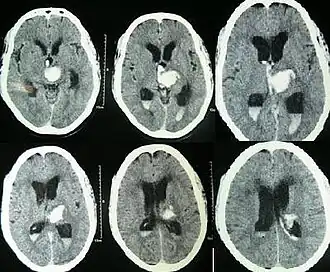

| Hydrocephalus as seen on a CT scan of the brain. The black areas in the middle of the brain (the lateral ventricles) are abnormally large and filled with fluid. | |

Hydrocephalus can occur due to birth defects (primary) or can develop later in life (secondary).[1] Hydrocephalus can be classified via mechanism into communicating, noncommunicating, ex vacuo, and normal pressure hydrocephalus. Diagnosis is made by physical examination and medical imaging, such as a CT scan.[1]